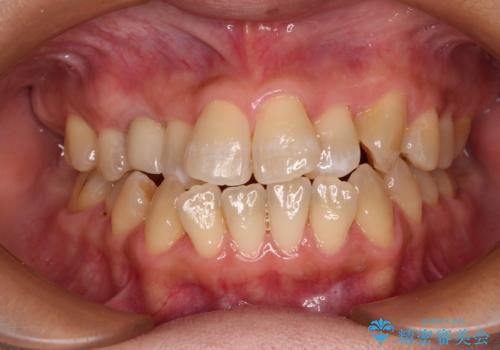

崩壊した歯は全て抜去し、他人から見える位置の歯はセラミッククラウンが装着され、整った口腔環境となりました。